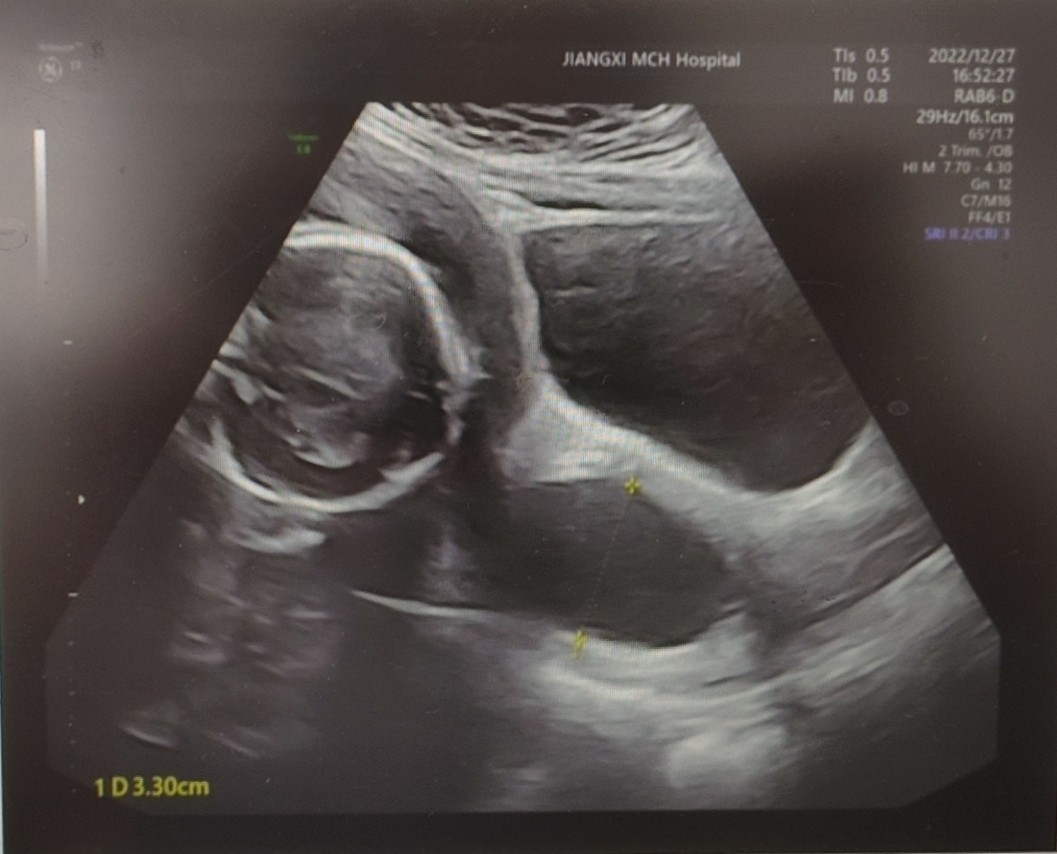

此后,赖华与刘女士一直保持着密切联系,时刻关注胎儿状态。孕21+1周时,刘女士再次出现阴道分泌物增多入院,随着孕周增加,其宫颈长度出现缩短趋势,在充分评估病情后,主任医师李勤为其进行了经阴道宫颈环扎术,术后刘女士病情稳定,小小的生命顽强地跳动在妈妈的子宫里。